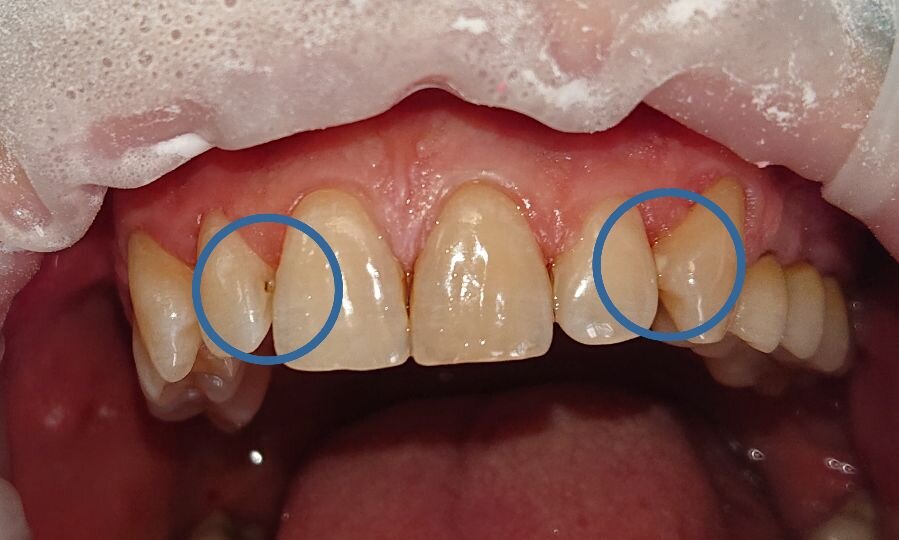

На первом фото на левом клыке (со стороны пациента) мы видим белое пятно - это очаг деминерализации, считающийся начальным кариесом. Обычно такие очаги не требуют лечения, поскольку дефекта эмали еще нет. В первую очередь пациент был обучен чистить зубы флоссом (зубной нитью), поскольку кариес на боковых поверхностях зубов - самый распространенный, особенно в этом случае. И чтобы такие белые пятна не переросли в кариес, кроме чистки важно использовать разные укрепляющие пасты и гели.

На двойке (зуб 1.2) мы уже видим дефект - без должного ухода белое пятно на клыке превратится в такой же кариес, как на двойке. Это кариозное поражение уже требует вмешательства - высверливания инфицированных тканей и замещения дефекта пломбировочным материалом.

На втором фото представлен еще один кариес на боковой поверхности зуба (у того же пациента) из-за отсутствия зубной нити в повседневной чистке зубов.